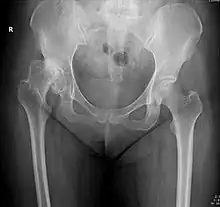

La subluxation de la hanche est la perte de contact, partielle et permanente, entre les deux surfaces articulaires que sont la tête fémorale et le cotyle.

Dans le langage médical, une luxation désigne un déplacement d'une surface articulaire par rapport à une autre. Il y a alors une rupture de continuité articulaire, comme si l'articulation se déboitait. Dans le cas d'une subluxation, la perte de contact n'est pas totale. Très douloureuse, la subluxation acquise de la hanche occasionne une impotence partielle voir complète du membre touché soit des difficultés voire une impossibilité à se servir de l'articulation de la hanche.

La subluxation est principalement la conséquence d'une malformation de la hanche congénitale dite dysplasie de la hanche ou de façon plus moderne dysplasie développementale de la hanche[1]. Elle est plus rarement la séquelle d'une luxation mal traitée. Elle peut aussi être la conséquence évolutive d'une infirmité motrice cérébrale avec tétraplégie[2].